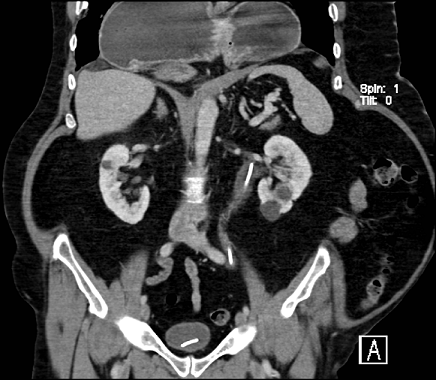

61 years old known case of bronchial asthma, chronic pancreatitis, presented with postprandial epigastric campy abdominal pain and vomiting for one month no history of trauma. Initial evaluation revealed paraesophageal hernia. EGD finding is grade II esophagitis with modular mucosa and superficial ulceration, Distal part of the funds, body and the Antrim were rolled back into thoracic cavity. Abdominal computed tomography (CT) showed undulating diaphragm and large complex hiatal hernia. The cardia is above the diaphragm. The entire stomach is in the chest, paraesophageal, right and left to esophagus. The patient is symptomatic and surgery done for him.